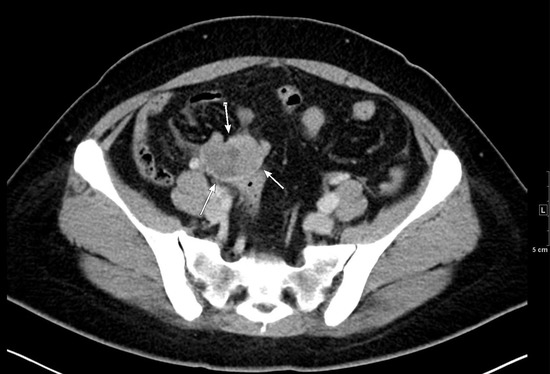

3.1.1. Case 1

3.1.2. Case 2

3.1.3. Case 3